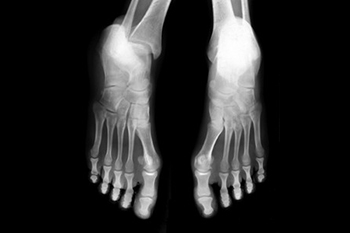

The human foot is a complex structure made up of bones, joints, muscles, and ligaments that work together to support movement and balance. It contains the tarsal bones in the rear and midfoot, the metatarsals in the arch and forefoot, and the phalanges that form the toes. These bones connect through joints that allow smooth motion while walking or running, as the alignment and function of these structures are essential for stability and shock absorption. When any part of the foot becomes strained or injured, pain and imbalance can occur. A podiatrist can evaluate the biomechanics of the foot, identify abnormalities, and provide treatments or custom orthotics for improved comfort. If you have persistent foot pain, it is suggested that you schedule a visit with a podiatrist who can treat various foot conditions.

Podiatric biomechanics is a particular sector of specialty podiatry with licensed practitioners who are trained to diagnose and treat conditions affecting the foot, ankle and lower leg. Biomechanics deals with the forces that act against the body, causing an interference with the biological structures. It focuses on the movement of the ankle, the foot and the forces that interact with them.